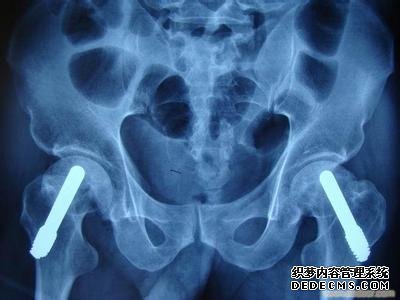

怎么医治髋关节疼痛比较好?关节疼痛,不仅仅会对患者的生活造成影响,还可能是妇科疾病的征兆,如果不及时治疗,疾病就可能恶化,造成更加严重的影响。那么,怎么医治髋关节疼痛比较好呢?

怎么医治髋关节疼痛比较好?专家推荐采用激光针刀松解术